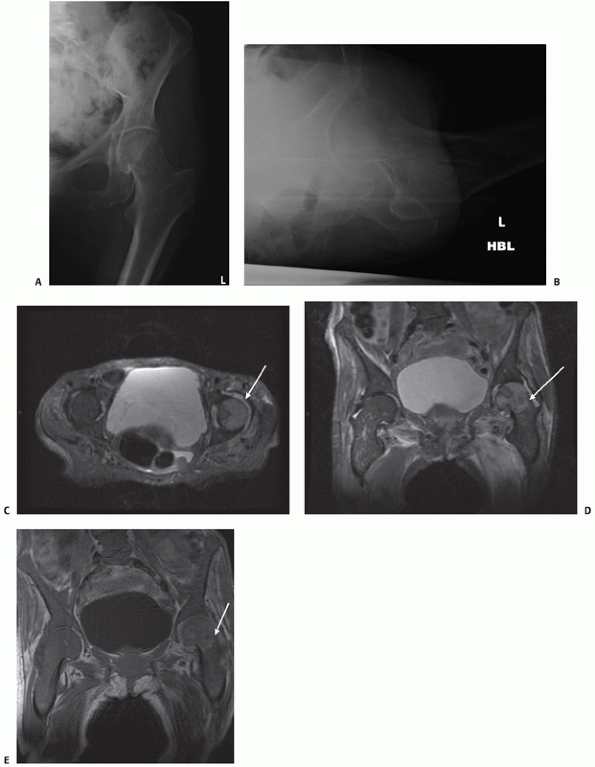

![]() |

|

FIGURE 47-1 AP and lateral radiographs of a displaced femoral neck fracture.

Anteroposterior (AP) and lateral radiographs are required. In the

majority of cases the diagnosis is clear on the AP radiograph.

Nonetheless the degree of displacement can be difficult to discern in

some patients and in others there may be doubt about the diagnosis. The

lateral radiograph may be difficult to acquire because of pain, but it

is useful in determining whether the fracture is present and whether it

is displaced. In 2% of cases the fracture may be difficult or

impossible to visualize on plain radiographs. In the past a technitium

bone scan was often considered a useful investigation in this situation.76

Although it is usually positive in cases with a femoral neck fracture,

there is the possibility of a false-negative in osteopenic bone if the

investigation is carried out within 48 to 72 hours of the fall. It is

also sensitive but not specific. CT

scanning is a more accurate investigation, but exposes the patient to further radation.